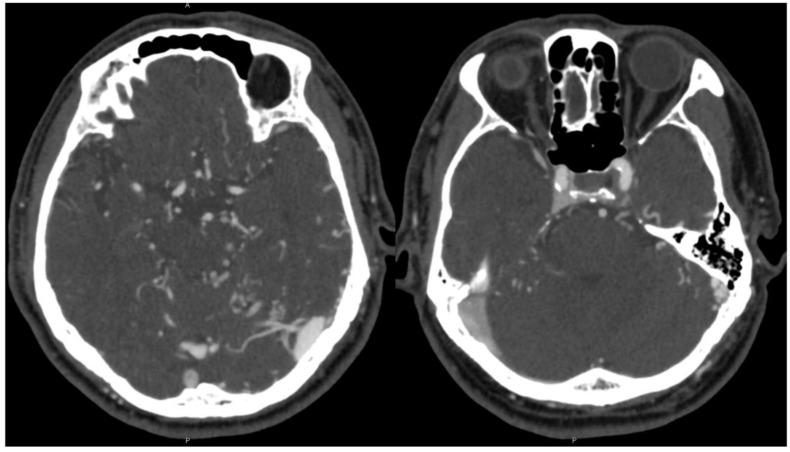

Dural arteriovenous fistulas (DAVFs) are rare intracranial vascular malformations that present with a variety of clinical signs and symptoms. Among these, intracranial hemorrhage is a severe complication. A 72-year-old male presented with headache and pulsatile tinnitus. Cerebral angiography revealed a Borden II/Cognard IIa+b DAVF. He underwent stage 1 transarterial embolization of the occipital artery which reduced shunting by 30%. Several attempts were made to access the fistula during stage 2 transvenous embolization, but it was not possible to access the left transverse sinus fistula site since there was no communication across the torcula from the right transverse sinus and the left inferior sigmoid-jugular bulb was occluded. Therefore, a single burr hole was drilled and direct access to the DAVF was achieved with a micropuncture needle under neuronavigational guidance. The left transverse-sigmoid sinus junction was then embolized with coils. After the procedure, angiography revealed that the DAVF was cured with no residual shunting. This case demonstrates how minimally invasive surgery provides an alternative method to access a DVAF when conventional transarterial and/or transvenous embolization treatment options are not possible. Each DAVF case has unique anatomy and physiology, and creative multi-disciplinary strategies can often yield the best results.

硬脑膜动静脉瘘(DAVF)是罕见的颅内血管畸形,可表现出多种临床体征和症状。其中,颅内出血是一种严重的并发症。一名72岁男性患者出现头痛和搏动性耳鸣。脑血管造影显示为Borden II/Cognard IIa+b型硬脑膜动静脉瘘。他接受了第一阶段枕动脉经动脉栓塞术,分流减少了30%。在第二阶段经静脉栓塞术期间,多次尝试进入瘘口,但由于右横窦与窦汇之间没有交通,且左乙状窦-颈静脉球闭塞,无法进入左侧横窦瘘口部位。因此,钻了一个单骨孔,并在神经导航引导下用微穿刺针直接进入硬脑膜动静脉瘘。然后用弹簧圈栓塞左侧横窦-乙状窦交界处。术后血管造影显示硬脑膜动静脉瘘治愈,无残余分流。该病例表明,当传统的经动脉和/或经静脉栓塞治疗方法不可行时,微创手术如何为进入硬脑膜动静脉瘘提供了一种替代方法。每个硬脑膜动静脉瘘病例都有独特的解剖结构和生理特点,创造性的多学科策略往往能产生最佳效果。